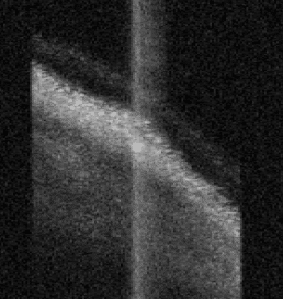

Allows you to directly measure the posterior corneal surface using SWEPT Source OCT

All measurement calipers are shown on the patented Cornea-to-Retina Scan allowing you to visually verify what structure has been measured.

Panoramic axial imaging